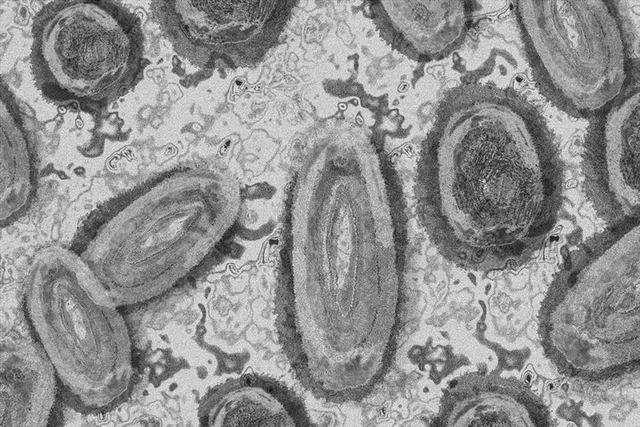

কেরলে মাঙ্কিপক্সে আক্রান্তের সংখ্যা আরো একজন বাড়লো

কেরলে মাঙ্কি পক্স আতঙ্ক